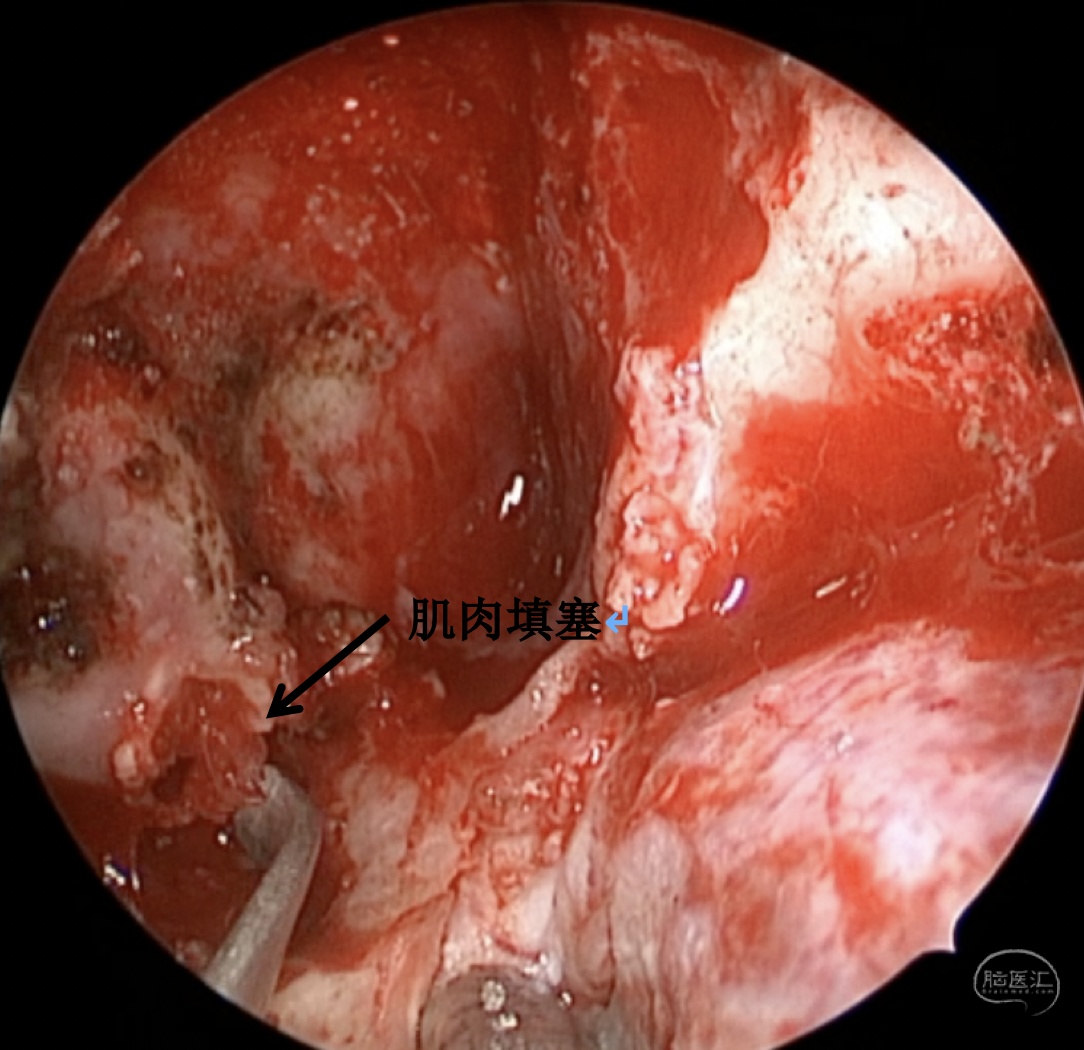

手术方案:内镜经鼻经翼突入路

术中情况: